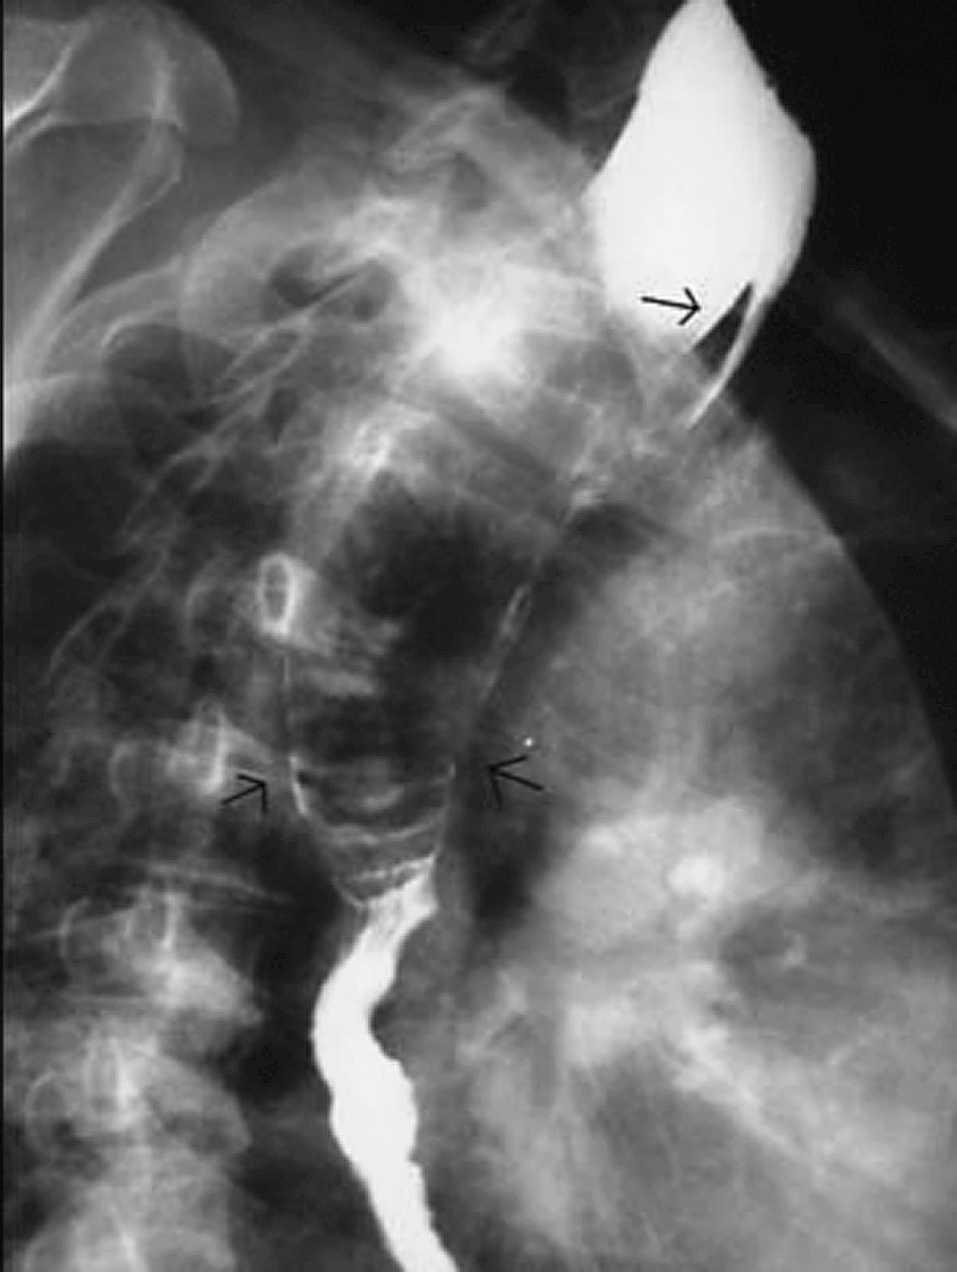

Paciente de 73 años, con antecedentes de exéresis de pólipos faríngeos hace 8 y 18 años y exéresis de lipoma de seno piriforme hace 6 meses, que es remitido por el otorrinolaringólogo por persistencia de clínica de disfagia alta tras la cirugía, sin otros síntomas. Se le practica una endoscopia digestiva, que informa de tumor submucoso de 8 cm en el tercio superior de esófago, que afecta desde boca de Killian hasta tercio medio esofágico. Con la sonda de ecoendoscopia se visualiza una masa ecogénica de 1,5 cm de diámetro que procede de submucosa e indica lipoma esofágico. En el tránsito baritado se aprecia un defecto de repleción de unos 10 cm de longitud que ocupa la totalidad de la luz esofágica (fig. 1). En la resonancia magnética se visualiza una tumoración del mediastino posterior hiperintensa en las imágenes potenciadas en T1 y T2, cuyo polo superior depende de esófago cervical. La tomografía computarizada cervicotorácica informa de una tumoración cervical intraesofágica de 10 × 3,5 × 4 cm, de características radiológicas compatibles con tejido graso. Ante estos hallazgos se decidió intervención quirúrgica. Mediante un abordaje por cervicotomía lateral izquierda, se procedió a la disección del esófago cervical y esofagotomía longitudinal; se visualizó una masa elástica que ocupaba la totalidad de la luz esofágica y se procedió a su extracción. La tumoración medía unos 10 cm, con una base de implantación fina en la pared posterior del esófago cervical (fig. 2). Se procedió a resección y posterior esofagorrafia. El postoperatorio fue satisfactorio, y se dio el alta al sexto día.

Fig 1. Tránsito baritado: ocupación total de luz esofágica por lipoma pediculado.

En cuanto al diagnóstico, fácilmente se reconocen en la endoscopia por su superficie lisa, elástica y de color amarillento. La biopsia endoscópica es difícil porque la mucosa tiende a retraerse con facilidad. En la ecoendoscopia se observa una lesión hiperecogénica y homogénea originada en la capa submucosa del esófago. El tránsito baritado muestra un defecto de repleción intraesofágico con dilatación esofágica. Con la introducción de la tomografía computarizada, el diagnóstico es más preciso y demuestra una masa de densidad grasa intraluminal. En ese caso hay que diferenciarlo de una entidad denominada lipomatosis esofágica, relacionada con el uso de esteroides. La imagen tomográfica del lipoma es una masa de densidad grasa central rodeada de la pared esofágica normal. En contraste, en la lipomatosis esofágica se observa un "doble anillo" por el depósito intramural de grasa, probablemente localizado entre las capas del músculo estriado de la porción proximal del esófago5. Esta apariencia es patognomónica, lo que facilita el diagnóstico diferencial entre ambas entidades y evita, por consiguiente, investigaciones y cirugías innecesarias.